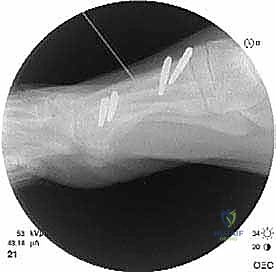

الخطوة الرابعة: الإطالة والطعوم العظمية (Bone Grafting)

يتم إبعاد طرفي العظم المقصوص بلطف للوصول إلى الطول التشريحي المطلوب (والذي تم حسابه مسبقاً في صور الأشعة). لملء الفراغ الناتج عن الإطالة، يتم استخدام طعم عظمي (Bone Graft).

* الطعم الذاتي (Autograft): غالباً ما يتم أخذ قطعة صغيرة من العظم من كعب المريض (عظم العقب) أو من عظم الحوض، وهو الخيار الأفضل لأنه يحفز الالتئام السريع.

* الطعم الصناعي أو العظم البنكي (Allograft): يمكن استخدامه في بعض الحالات لتجنب إحداث جرح إضافي.

الخطوة الخامسة: التثبيت الداخلي القوي (Internal Fixation)

لضمان التئام العظم في وضعه الجديد والطويل، يجب تثبيته بقوة شديدة. يستخدم الدكتور هطيف أحدث الشرائح المعدنية التيتانيوم ذات الزاوية الثابتة (Locking Plates) والمسامير الدقيقة. هذا التثبيت القوي يمنع أي حركة بين العظام ويسمح ببدء العلاج الطبيعي في وقت مبكر.